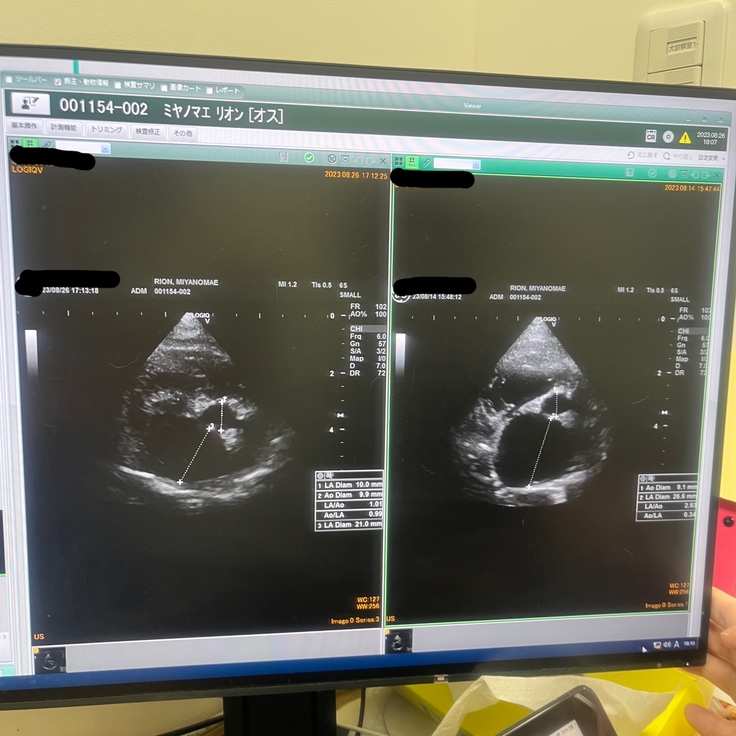

獣医師の説明によると、健康な子の心臓の大きさの3倍腫れ上がっています。と、、、

かかりつけ病院の診断書(病院名は隠してあります。先生の掲載許可済み)

手術を行う病院の診断書(病院名は隠してあります。先生の掲載許可済み)

12日間の投薬のおかげでほんの少しだけ小さくなったとの事です。

検査結果